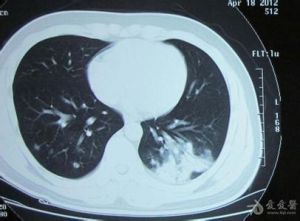

X線胸片?即取病灶組織少許,置載玻片上,加生理鹽水1~2滴,用細針將組織搗碎,在顯微鏡下觀查,如見菌絲和孢子,即可確診。或以結節內壞死物接種於馬鈴薯培勞基或由麥芽糖4g、蛋白腖2g、瓊脂1.8g、蒸餾水100m1,製成的培養基上,在34℃下經10~l2小時的培養,出現白色薄膜菌落,再經22~24小時形成孢子,鏡檢培養物即可作出肯定診斷。